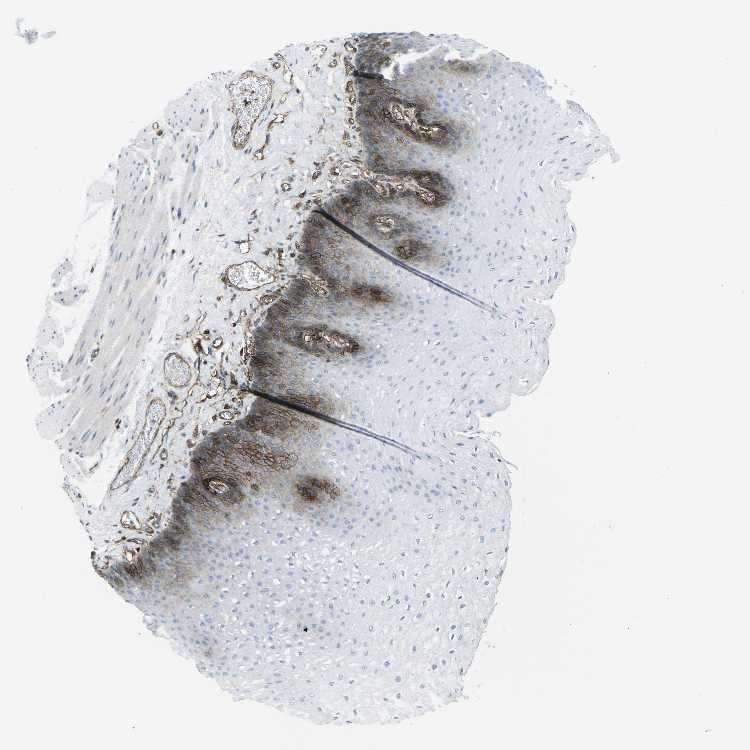

ESOPHAGUS - Antibody stainingi

Antibody staining in the annotated cell types in the current human tissue is reported as not detected, low, medium, or high, based on conventional immunohistochemistry profiling in selected tissues. This score is based on the combination of the staining intensity and fraction of stained cells.

Each image is clickable and will lead to virtual microscopy that enables deeper exploration of all samples and also displays staining intensity scores, fraction scores and subcellular localization as well as patient and tissue information for each sample.

Antibody CAB015418

Squamous epithelial cells Low